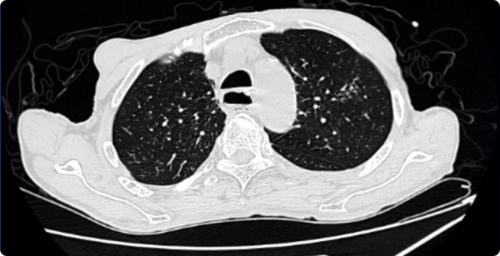

入院时CT: